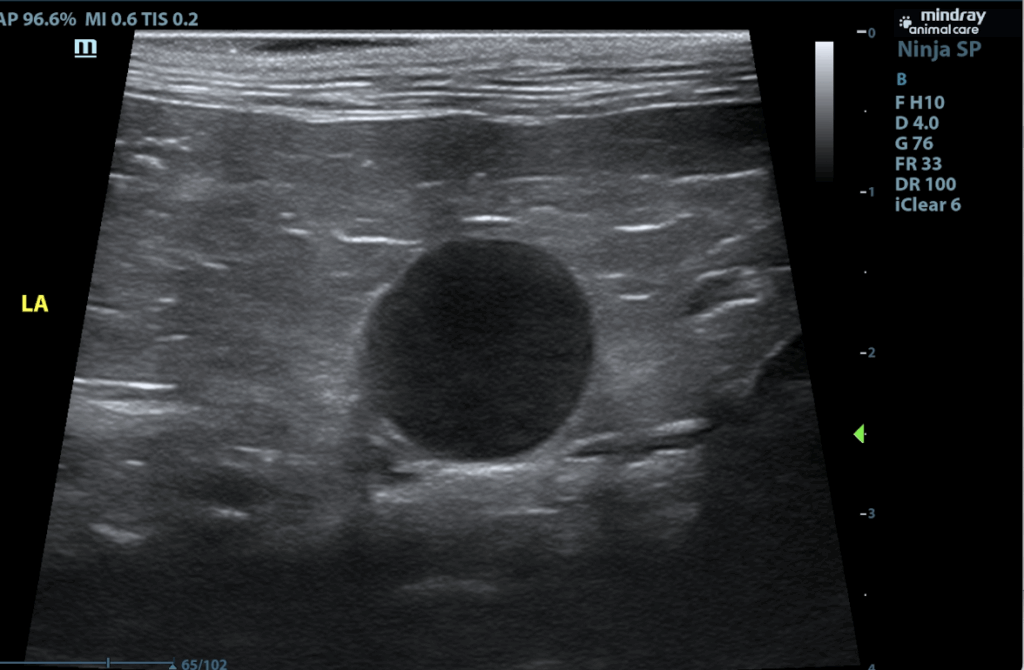

The right adrenal gland is normal in size (0.38 cm at cranial pole and 0.31 cm at caudal pole), shape and overall architecture, echogenicity and echotexture. Visible surrounding vasculature appears normal. The left adrenal gland is enlarged, measuring 1.8 cm long x 1.2 cm thick at the caudal pole, with mild heterogeneous parenchymal changes and an overall egg-shaped hypoechoic appearance, with swollen capsular expansion noted but no evidence of capsular escape or vascular invasion.

- Left adrenal mass.